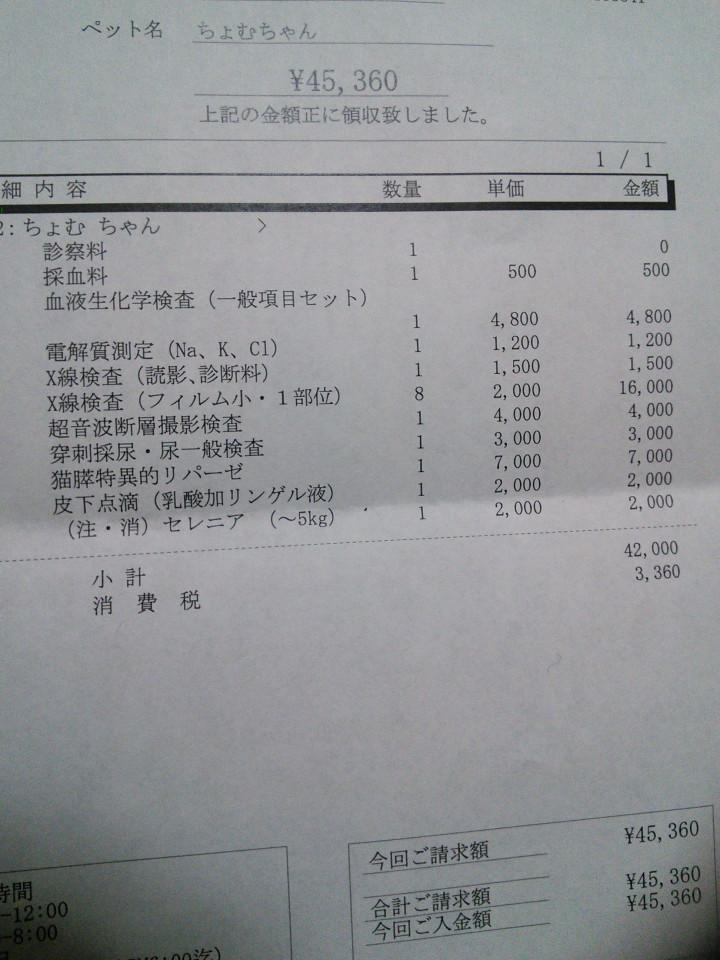

検査しまくりの1日……

血液検査、尿検査ではまるっきり問題なし。

なのでレントゲンとエコー。

結腸部分に何かある。

誤飲した異物などではない。

腸閉塞か?

バリウム飲んで胃腸の動きを見る。

膵臓も近い部分なので、一応膵炎などの検査。

半日入院状態。

結果

わからん(´<_` )フッ

バリウムも綺麗に流れ、腸閉塞でもない。

なのでひとまず急を要する事態ではなし。

もしかすると、腸に不着物がある?

消化吸収されない液体?

一週間後患部がどうなってるかまたレントゲン。

これが今日のレントゲン☟☟☟

白いのと、その周りに何やらつぶつぶが……

ただの炎症なら良いのだが……(--;)